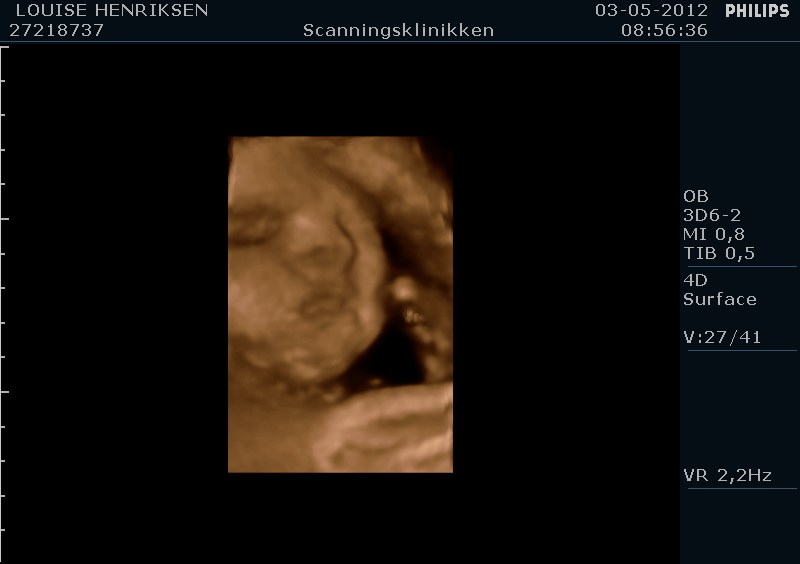

I dag skulle manden overraskes med en 4 d scanning.... og hans far var også med det var også en overraskelse, samt den lille prins....han fik bind for øjene og vi kørte mod scanning klinikken.... vi fik nogle gode sekvenser af bettemanden.. men han fylder en del derinde nu, så billederne blev ikke voldsomt gode.. men nogle fik vi dag...jeg skulle i morgen være 32 fulde uger.. mne scanningen i dag vidste34+4 dage yiarks.... jeg skal til at være færdig med den bachelor..... han vejede efter målene 1871 gram.....

så han var en fin basse...

Sikke nogle fine billeder